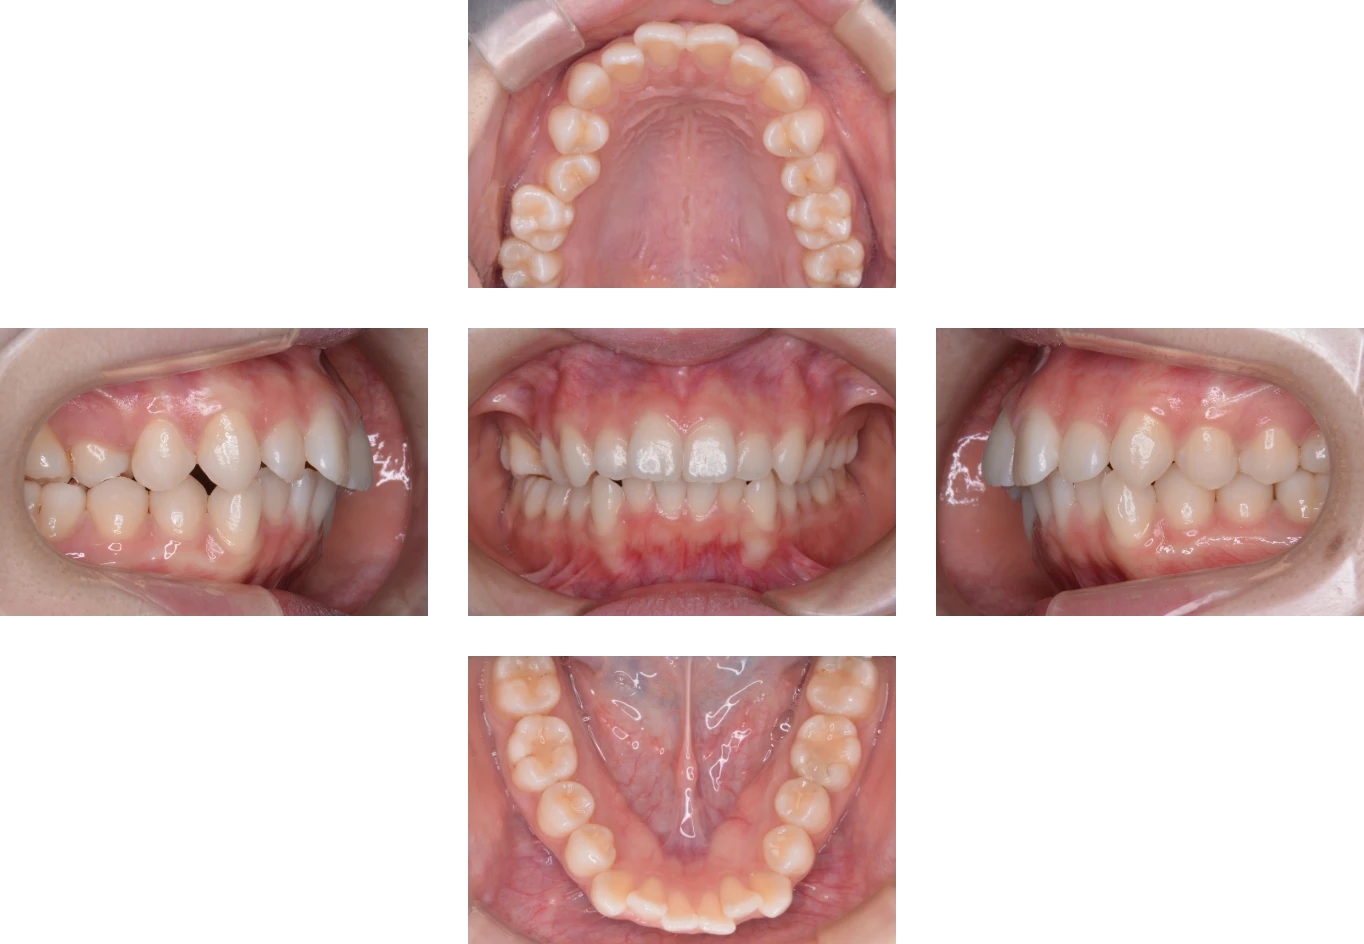

Case2

| 主訴 | すきっ歯と出っ歯 |

| 診断名 | 上顎前突 |

| 年齢 | 33歳 |

| 治療に 用いた装置 |

リンガルブラケット矯正装置(エッグブラケット)、 マルチブラケット装置 |

| 抜歯部位 | 非抜歯 |

| 治療期間 | 2年2ヶ月 |

| 治療費用 | 1,085,000円 |